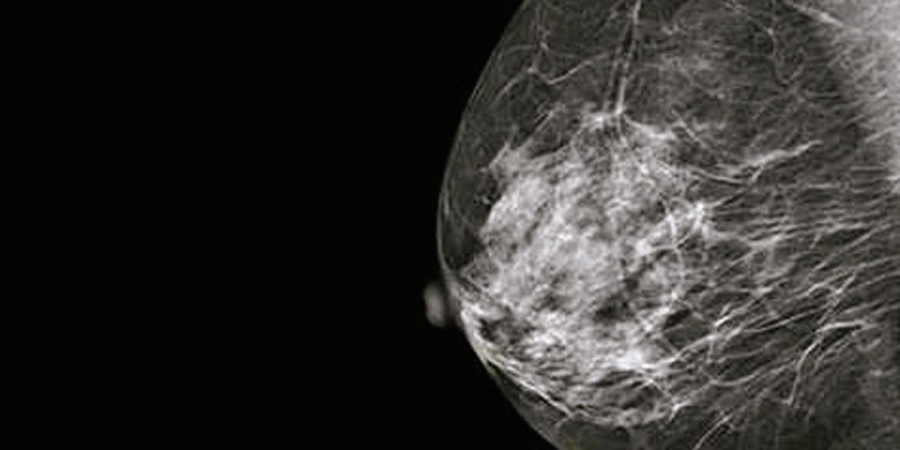

La mamografía es una potente herramienta con la que cuentan los médicos para detectar el cáncer de mama, además de diagnosticar, evaluar y llevar adelante el seguimiento de quienes padecen la enfermedad. La Dra. Blanco explica que “la mamografía es una técnica radiológica especialmente compleja debido a que la mama está constituida por tejido adiposo, tejido fibro-conectivo y tejido glandular. Los tres se distribuyen sin un patrón fijo y varían en cada mujer por edad, espesor, lactancia o situación hormonal. Los tres tejidos presentan, además, una densidad radiológica similar frente a los RX respecto a las patologías que requiere buscar (como “masas” y microcalcificaciones)”. Debido al pequeño tamaño de las algunas estructuras patológicas que permitirían una detección precoz del cáncer, señala la investigadora, la mamografía se convierte en el estudio radiológico más dependiente de los factores de calidad del mamógrafo y de todos los elementos complementarios del estudio. En particular, de la compresión de la mama durante la realización de la mamografía. Esa comprensión es necesaria ya que produce una reducción uniforme del espesor de la mama, optimiza el contraste radiológico, permite obtener mayor nitidez y detalle, y mayor resolución de los bordes de las estructuras glandulares, reduce la dosis de radiación que recibe el paciente, inmoviliza el órgano disminuyendo la borrosidad por el movimiento que pudiera ocurrir, y separa estructuras glandulares sobrepuestas, facilitando su interpretación. Por lo tanto, resalta Blanco, la compresión en la mamografía es un importante y fundamental componente de la técnica y del control de calidad. Sin embargo, constituye un tema álgido y controversial de acuerdo a los comentarios de pacientes.

Para la investigación, el equipo empleó dos muestras de 402 y 268 mamografías, respectivamente, obtenidas en dos centros de diagnóstico que cuentan con el mismo equipamiento -mamógráfo digital directo de 2014-, pero con diferentes técnicas de compresión. Las edades de las pacientes variaron entre los 21 y los 50 años.

El trabajo cuantificó la tolerancia a la compresión de la mama con valores de 1 (sin problemas) a 4 (mucha incomodidad o molestia). “Un aumento del 5% en promedio en la fuerza de compresión permitió disminuir significativamente las dosis impartidas en los estudios. En la población analizada, un 35% de compresión parece ser un valor adecuado para garantizar dosis muy aceptables. Con respecto al estado de incomodidad o molestia declarado por las pacientes, se deduce que, a la luz de la muestra total obtenida, no parece estar vinculado a variaciones normales de la fuerza de compresión aplicada ni al hecho de tratarse o no del primer estudio que se efectúa la paciente”, indica la investigadora.

La compresión en mamografía, siguiendo los estándares internacionales de una fuerza de entre 80 y 120 newtons, es efectiva en cuanto a la reducción de dosis, sin por eso ser insoportable para la paciente. El presente trabajo es, sin dudas, una contribución respecto de las buenas prácticas en los procedimientos mamográficos.